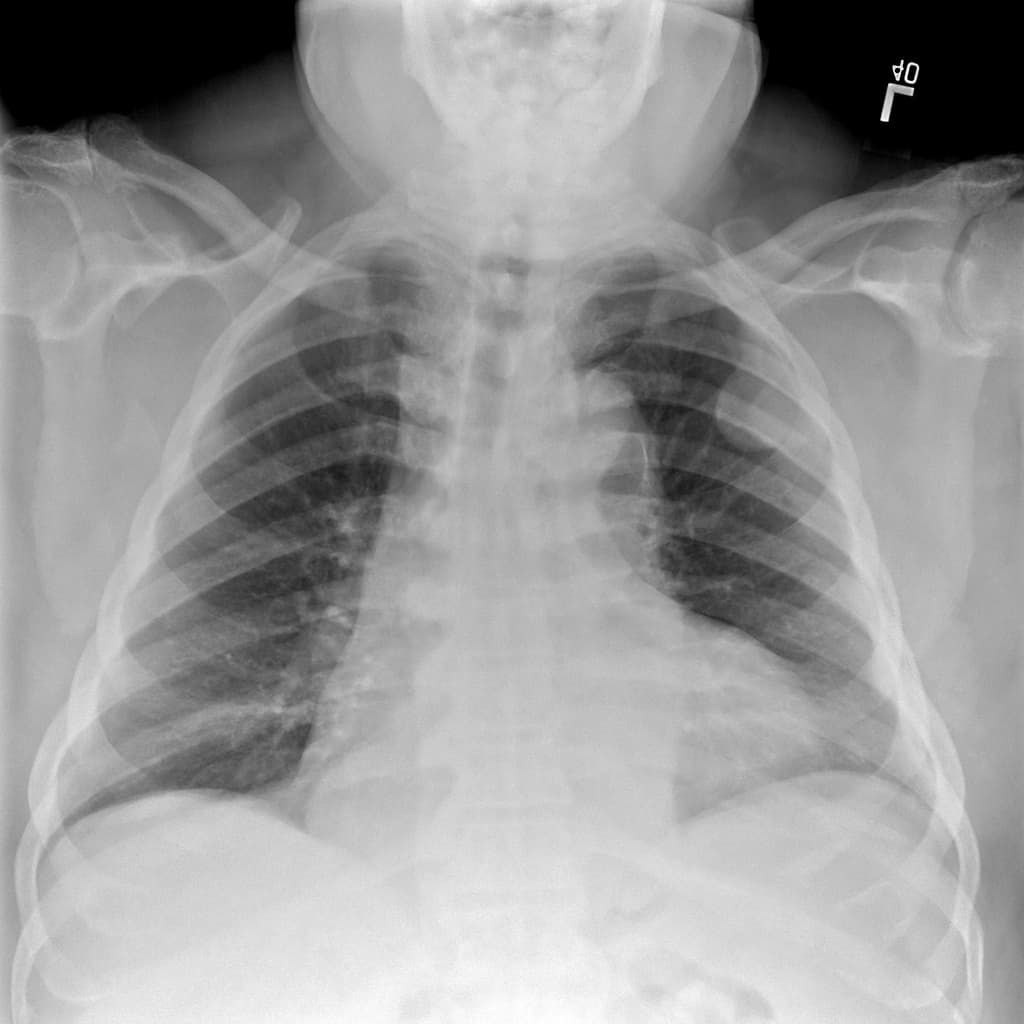

Chụp X-quang ngực (Radiography)

Có thể thấy một khối mờ đồng đều, mật độ mềm, thường nằm sát thành ngực hoặc dọc theo khe liên thùy.

Trong nhiều trường hợp, X-quang ngực có thể bình thường nếu khối u nhỏ hoặc nằm ở vị trí khó phát hiện 4.